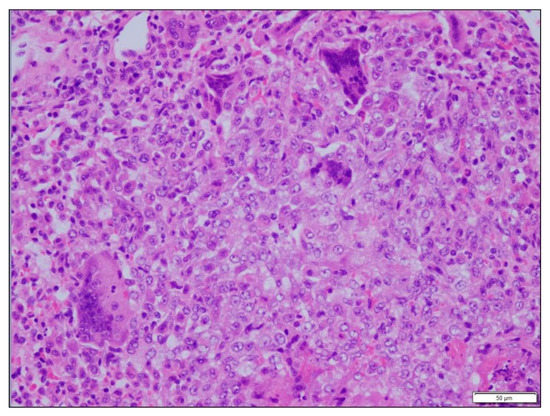

3.3. Histopathological Findings